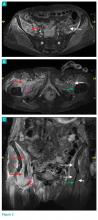

Axial and coronal edema-sensitive images of the pelvis demonstrated edema (increased signal) within the right psoas, iliacus, and iliopsoas muscles (red arrows, Figures 2a-2c), which were in contrast to the normal pelvic muscles on the left side (white arrows, Figures 2a-2c).

Figure 2.

The MRI studies also demonstrated a torn right iliopsoas tendon (magenta arrow, Figures 2b and 2c) in contrast to the normal left tendon (green arrow, Figures 2b and 2c). The sacrum was noted to be normal in signal (white asterisks, Figure 2a).